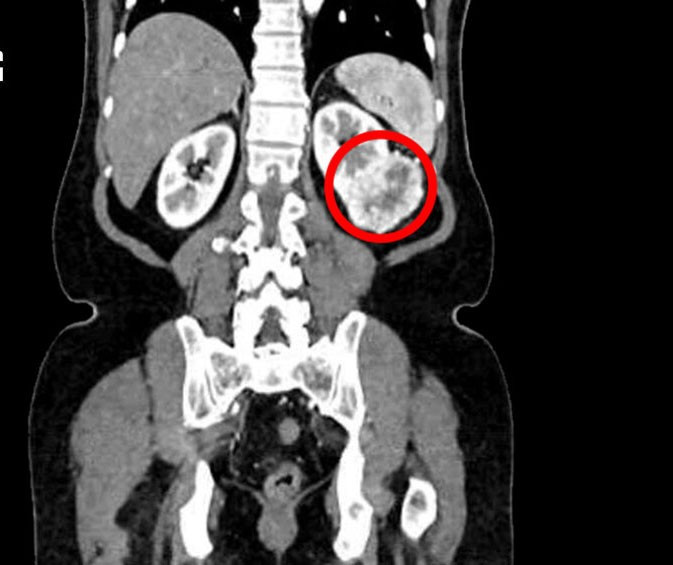

Để chắc chắn hơn, vợ chồng ông đến Bệnh viện Đa khoa Tâm Anh TP HCM kiểm tra một lần nữa. Kết quả chụp cắt lớp vi tính cho thấy, ông Hiền có một khối u ở thận trái kích thước 6 cm, nằm ở 1/3 giữa thận, lấn sâu vào xoang thận, nghi ngờ ung thư tế bào thận, một loại ung thư thường gặp của thận.

Khối u thận trái nằm ở 1/3 giữa thận, ăn sâu vào xoang thận, nghi ngờ ung thư. Ảnh: Bệnh viện Đa khoa Tâm Anh TP HCM - Ảnh BVCC